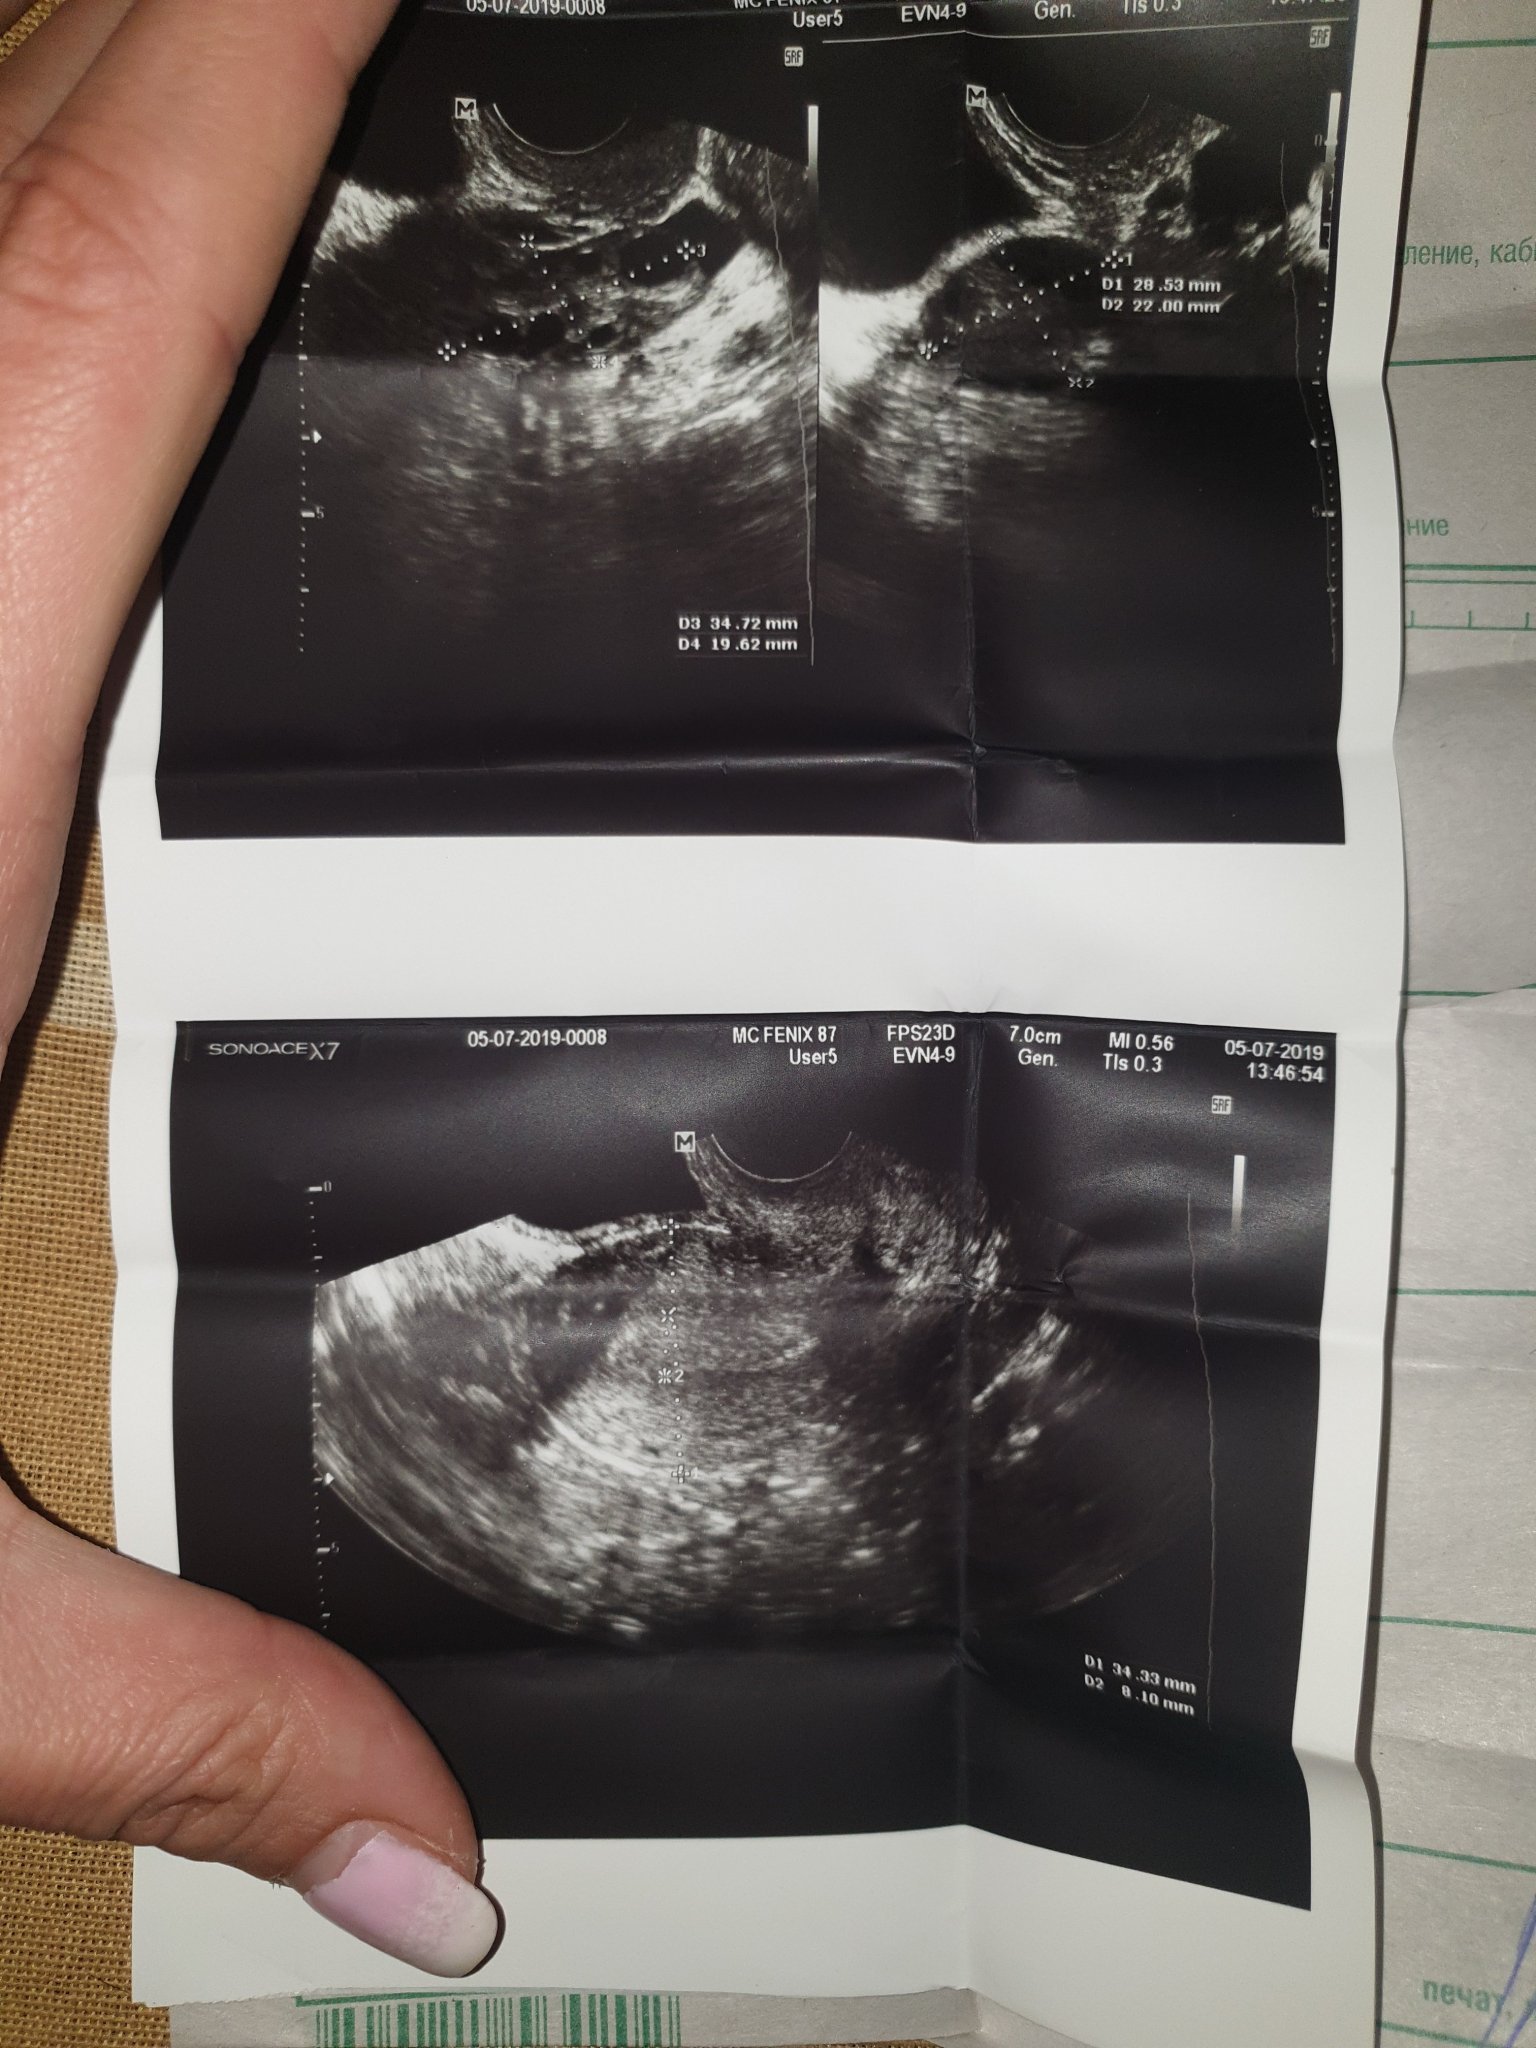

Здравейте. Предварително се извинявам, но не открих къде мога да задам въпроса си. Преди известно време бях на преглед при гинеколог, тъй като имам болки в десния яйчник. Прегледа ме за минута, и отсече нищо ти няма. Даде ми снимка, и си тръгнах. Забравих за случая, но ето ,че отново имам същите болки. Разрових се и намерих снимката. Та въпросът ми е: Има ли, според вас нещо на тази снимка,или аз си въобразявам? Благодаря предварително!

Благодаря. Гледаха ме с трансвагинален ехограф. Че имам киста, ми подсказва това, което е обозначено с милиметри, тъй като имам кисти и на гърдите, и снимките там са същите. Знам,че най-добрият вариант е да отида отново, просто сега съм неразположена, и няма как. Затова писах тук. Simple Smile